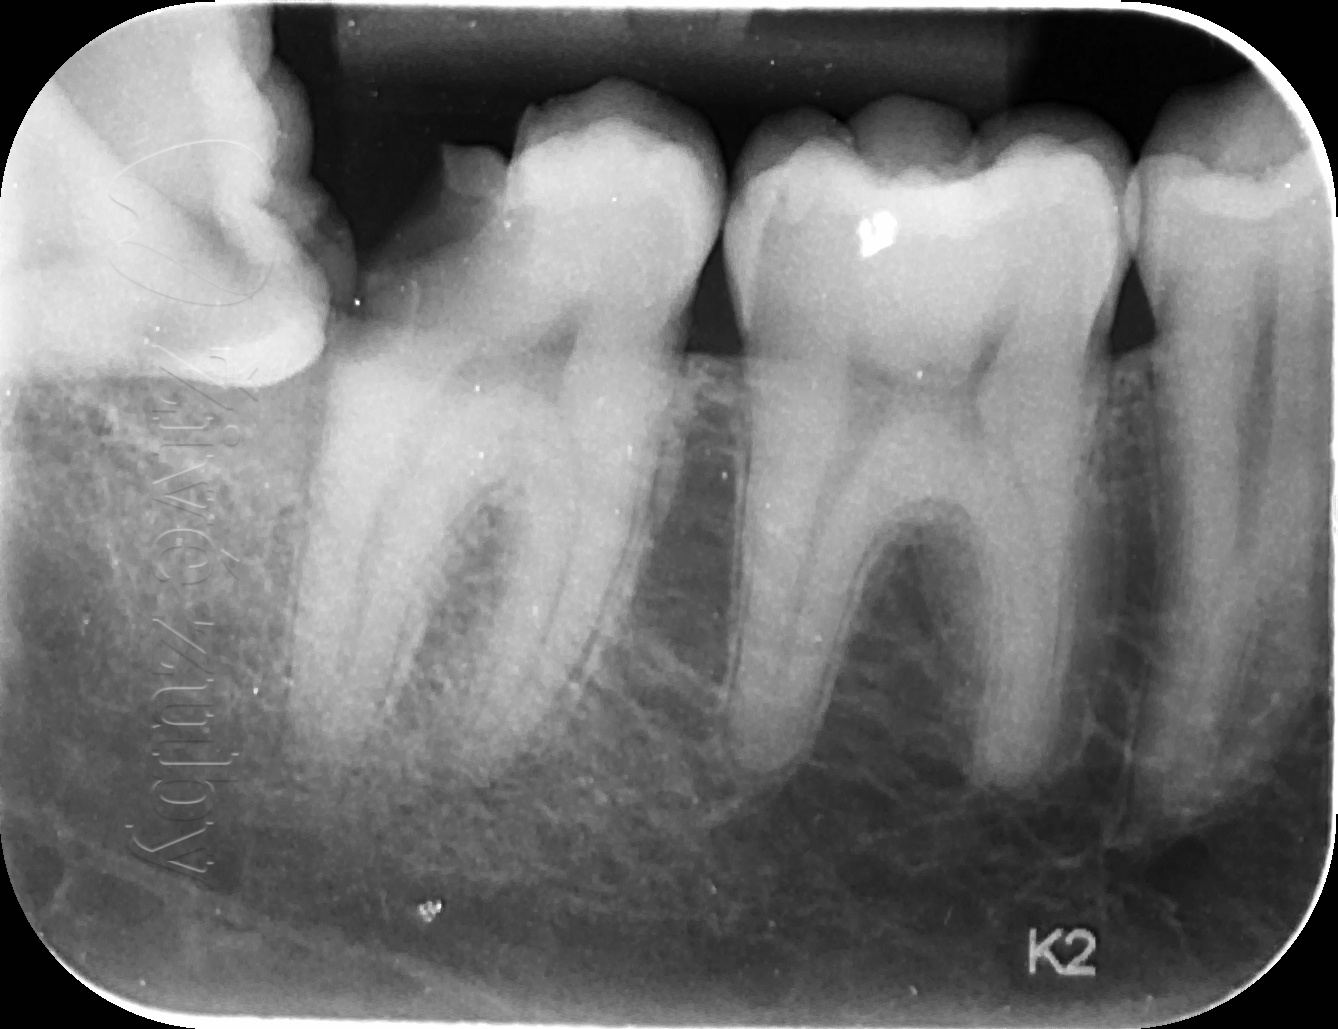

Ošetření hlubokých kazů

Výchozí stav  ——-> Kontrola po 2 letech ——--> Kontrola po 3 letech